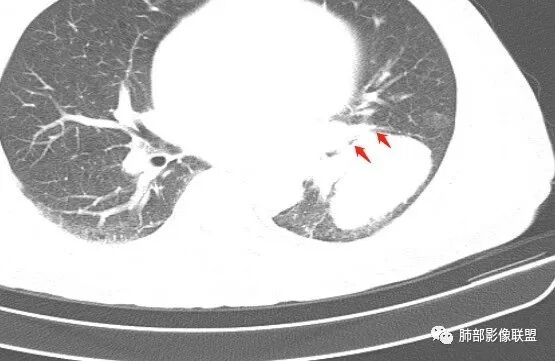

恶性肿瘤没有问题,这一层如果是指状突起我考虑小细胞癌

病史:男,70岁,咳嗽;影像:肺门淋巴结,淋巴结内血管毛糙不规则,静脉期,转移大,左心房左下静脉下支是否有累及。主体病灶,呈扇形,沼泽样,指状突起。肺气肿并不明显,左侧少许,左上叶支气管狭窄,肺窗点状凸起,纵膈窗并没有,考虑淋巴结压迫所致。老王曾经说过,小细胞来不及跑得快,胸膜目前没有积液是否是这个原因?诊断:恶性,小细胞肺癌;鉴别:鳞癌,不太像,其他神经类分泌恶性肿瘤;处置:经皮穿刺或EBUS。

1鸭蹼状突起、腊肠样尾巴、指状突起、蠕虫、分支及条状

因为病灶沿支气管粘膜下及周围血管生长,走形方向与支气管一致,所以支气管血管周围生长也是SCLC的典型征象;

1.左肺下叶近肺门区肿块,肿块外围大,内带小,提示外围向中央生长,符合周围型SCLC沿支气管方向生长。

2.病灶边缘光滑,未见明显分叶、毛刺,符合神经内分泌癌、癌肉瘤及间叶来源肿瘤。

3.病灶内密度偏低,穿行血管未见明显异常,轻度不均匀强化,为乏血供病灶。病灶内可疑坏死区,未见空洞;乏血供符合SCLC,但坏死区不符合。

4.病灶区支气管以受压推移为主,管腔不规则,腔内通而不畅,提示病灶粘膜下为主,符合SCLC迁徙蔓延或间叶来源肿瘤。

5.病灶内有血管走行,血管局部受压,但是强化考虑为乏血供,提示病灶内肺动脉并不是供血血管,只是病灶侵袭性强把血管包埋而已,为血管包埋征;血流面光滑,血管包埋符合SCLC。

6.左肺门淋巴结肿大,与病灶局部融合分界不清,呈冰冻肺门;而纵隔内未见肿大淋巴结,冰冻肺门符合SCLC,但是病灶主体那么大,纵隔内没有明显肿大淋巴结,不是很符合SCLC娘小崽大的特点。

7.未见明显阻塞性炎症及阻塞性肺不张,更加提示病灶从外围向中央侵犯,符合SCLC罕见阻塞性肺不张。